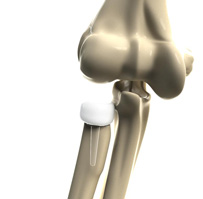

Partial Elbow Replacement

Partial elbow replacement is a surgical procedure performed to replace only the damaged or diseased portions of your elbow joint